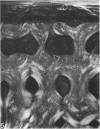

The dorsal cortex of the equine third metacarpal mid-diaphyseal bone was characterised during growth by the histological and microradiographic examination of specimens from 30 horses ranging in age from 2 months to 8 y. Bone from horses aged less than 6 months was characterised by rapid periosteal apposition of circumferential trabeculae of woven bone that were next connected by radial trabeculae to the parent cortex. Deposition of lamellar bone on the inner trabecular surfaces resulted in rows of primary osteons. Replacement of primary bone occurred only after 4 months of age and preferentially in the woven interstitial bone separating rows of primary osteons formed in the postnatal periosteal cortex. Resorption cavities and incompletely filled secondary osteons characterised bone of 1 and 2-y-old horses. Bone from horses older than 3 y contained several generations of secondary osteons, fewer resorption spaces and incompletely filled osteons, and had a greater portion of circumferentially oriented collagen fibres than bone from younger horses. Bone from horses older than 5 y had large resorption cavities characterised by irregular boundaries. We propose that the process of periosteal bone tissue apposition observed in growing foals be called 'saltatory primary osteonal bone formation' and that this process results in faster cortical expansion and larger total surface area for bone deposition than circumferential lamellar, simple primary osteonal, and plexiform mechanisms of periosteal bone formation. We speculate that bone from 1 and 2-y-old horses would be more susceptible to fatigue microdamage resulting from compressive loads because of high porosity, few completed secondary osteons and low proportion of circumferentially oriented collagen fibres.